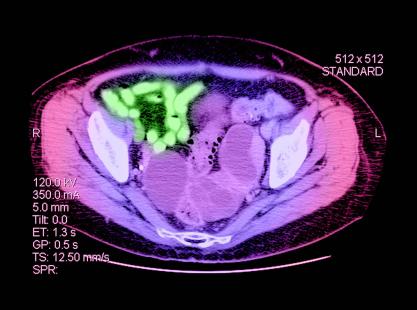

L’étude concerne 90 patientes atteintes de récidive d’un cancer ovarien sensible au platine, de haut grade ou BRCA positif, assignés après randomisation soit à l’olaparib seul (400 mg deux fois par jour) soit à l’olaparib (200 mg deux fois par jour) associé au cediranib (30 mg/j). Les groupes ont été stratifiés selon la présence d’une mutation BRCA et selon l’existence d’un traitement anti-angiogénique antérieur. Les patientes, âgés de 58 ans en moyenne, ont été recrutées entre octobre 2011 et juin 2013.

En mars 2014, la survie sans progression a été de 16,6 mois dans le groupe recevant l’association des deux traitements contre 9 mois dans le groupe assigné à l’olaparib seul (HR 0,42 : 95 % ; CI [0,23-0,76], p = 0,005). Le taux de réponse objectif a été de 80 % pour les patientes assignées à la combinaison thérapeutique contre 48 % pour le groupe assigné à l’olaparib seul (p = 0,002). Les effets secondaires, fatigue, diarrhées, hypertension, ont été plus fréquents dans le groupe de patientes recevant l’association.